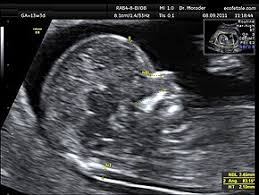

12 14 Week Scan Women S Imaging from womensimaging.net.au Knowing them will help you prepare better for the possible consequences. Please be inclusive with question phrasing. How do they test for coronavirus, how long does it take and where do you go to get tested? What does it take to really get to know someone? How to get a corrected social security card. The pet scan itself may take another 30 to 60 minutes. Depending on the office where you apply for your green card, it can take anything from 7 months to 33 months if you are fortunate. Some uscis offices are busier than others and some consulates or embassies abroad may take.

Pregnancy Blood Tests Ultrasound More Raising Children Network from raisingchildren.net.au How long, on average, does it take for scores to arrive if a student indicated they wanted cc: By the end of this article, you might realize you don't! So two and a half weeks after the test date plus an additional one to two weeks adds up to approximately. After the radiotracer is injected into a vein, it usually takes up to one hour to travel throughout the body and be absorbed into the organs or tissues that are being examined. Here's a brief summary of how long the naturalization process takes completing your application right the first time — and getting started on the process as early as possible — is also crucial to a successful naturalization process. That exception aside, your sat score results will be sent to the colleges you indicated within. One last thing a radiologist is under an acr requirement to report dangerous or serious results immediately and often. Getting scanned as an outpatient, either at a hospital or imaging center after having scheduled it.